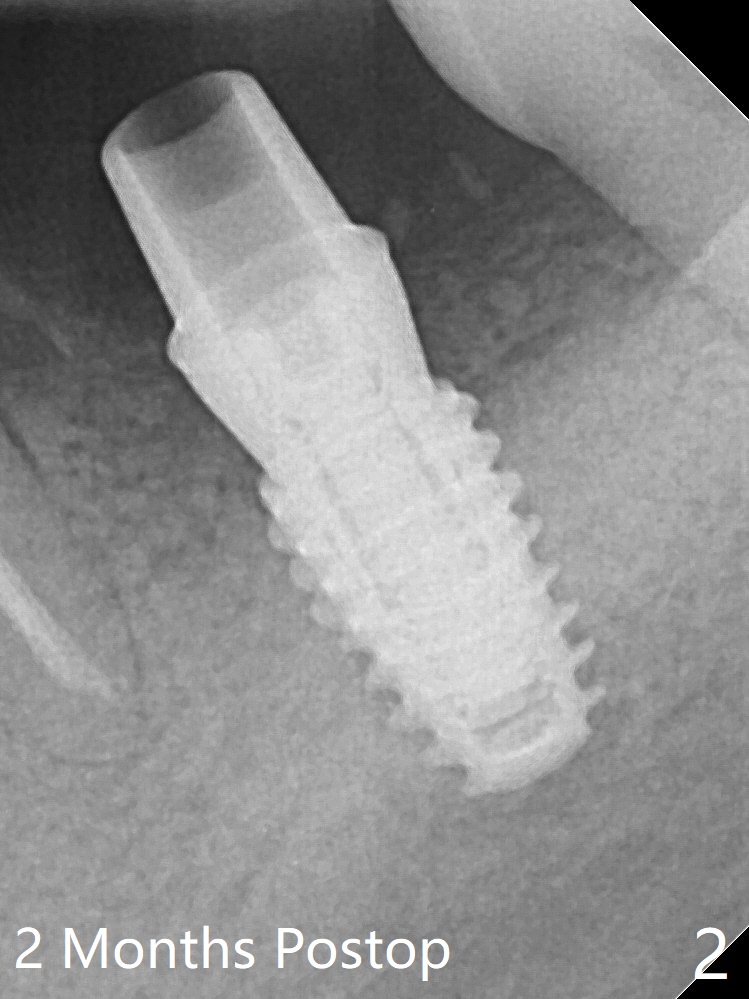

A 4.5x7 mm implant is placed at #31 with >50 Ncm due to the dense bone (Fig.1). The mesiodistal space is so small that a small abutment has to be used (4.5x4(3) mm). Partially because of the dense bone and partially nervousness, the patient feels pain with infiltration during osteotomy. The pain reduces when drill pressure decreases. Bone shaving has to be removed frequently to relieve pressure. PA is taken after the abutment is torqued to 30 Ncm after cleaning (2 months postop, Fig.2). In fact it has to be removed due to subgingival margin and inflamed gingiva. A 5.5x5(3) mm healing abutment is placed.